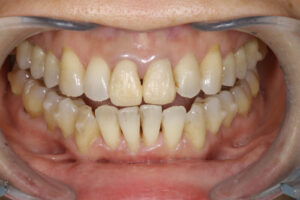

Invisalign correction failure

全く噛んでない

インビザラインで失敗した45歳女性

骨から歯が飛び出ている

奥歯が噛んでいない